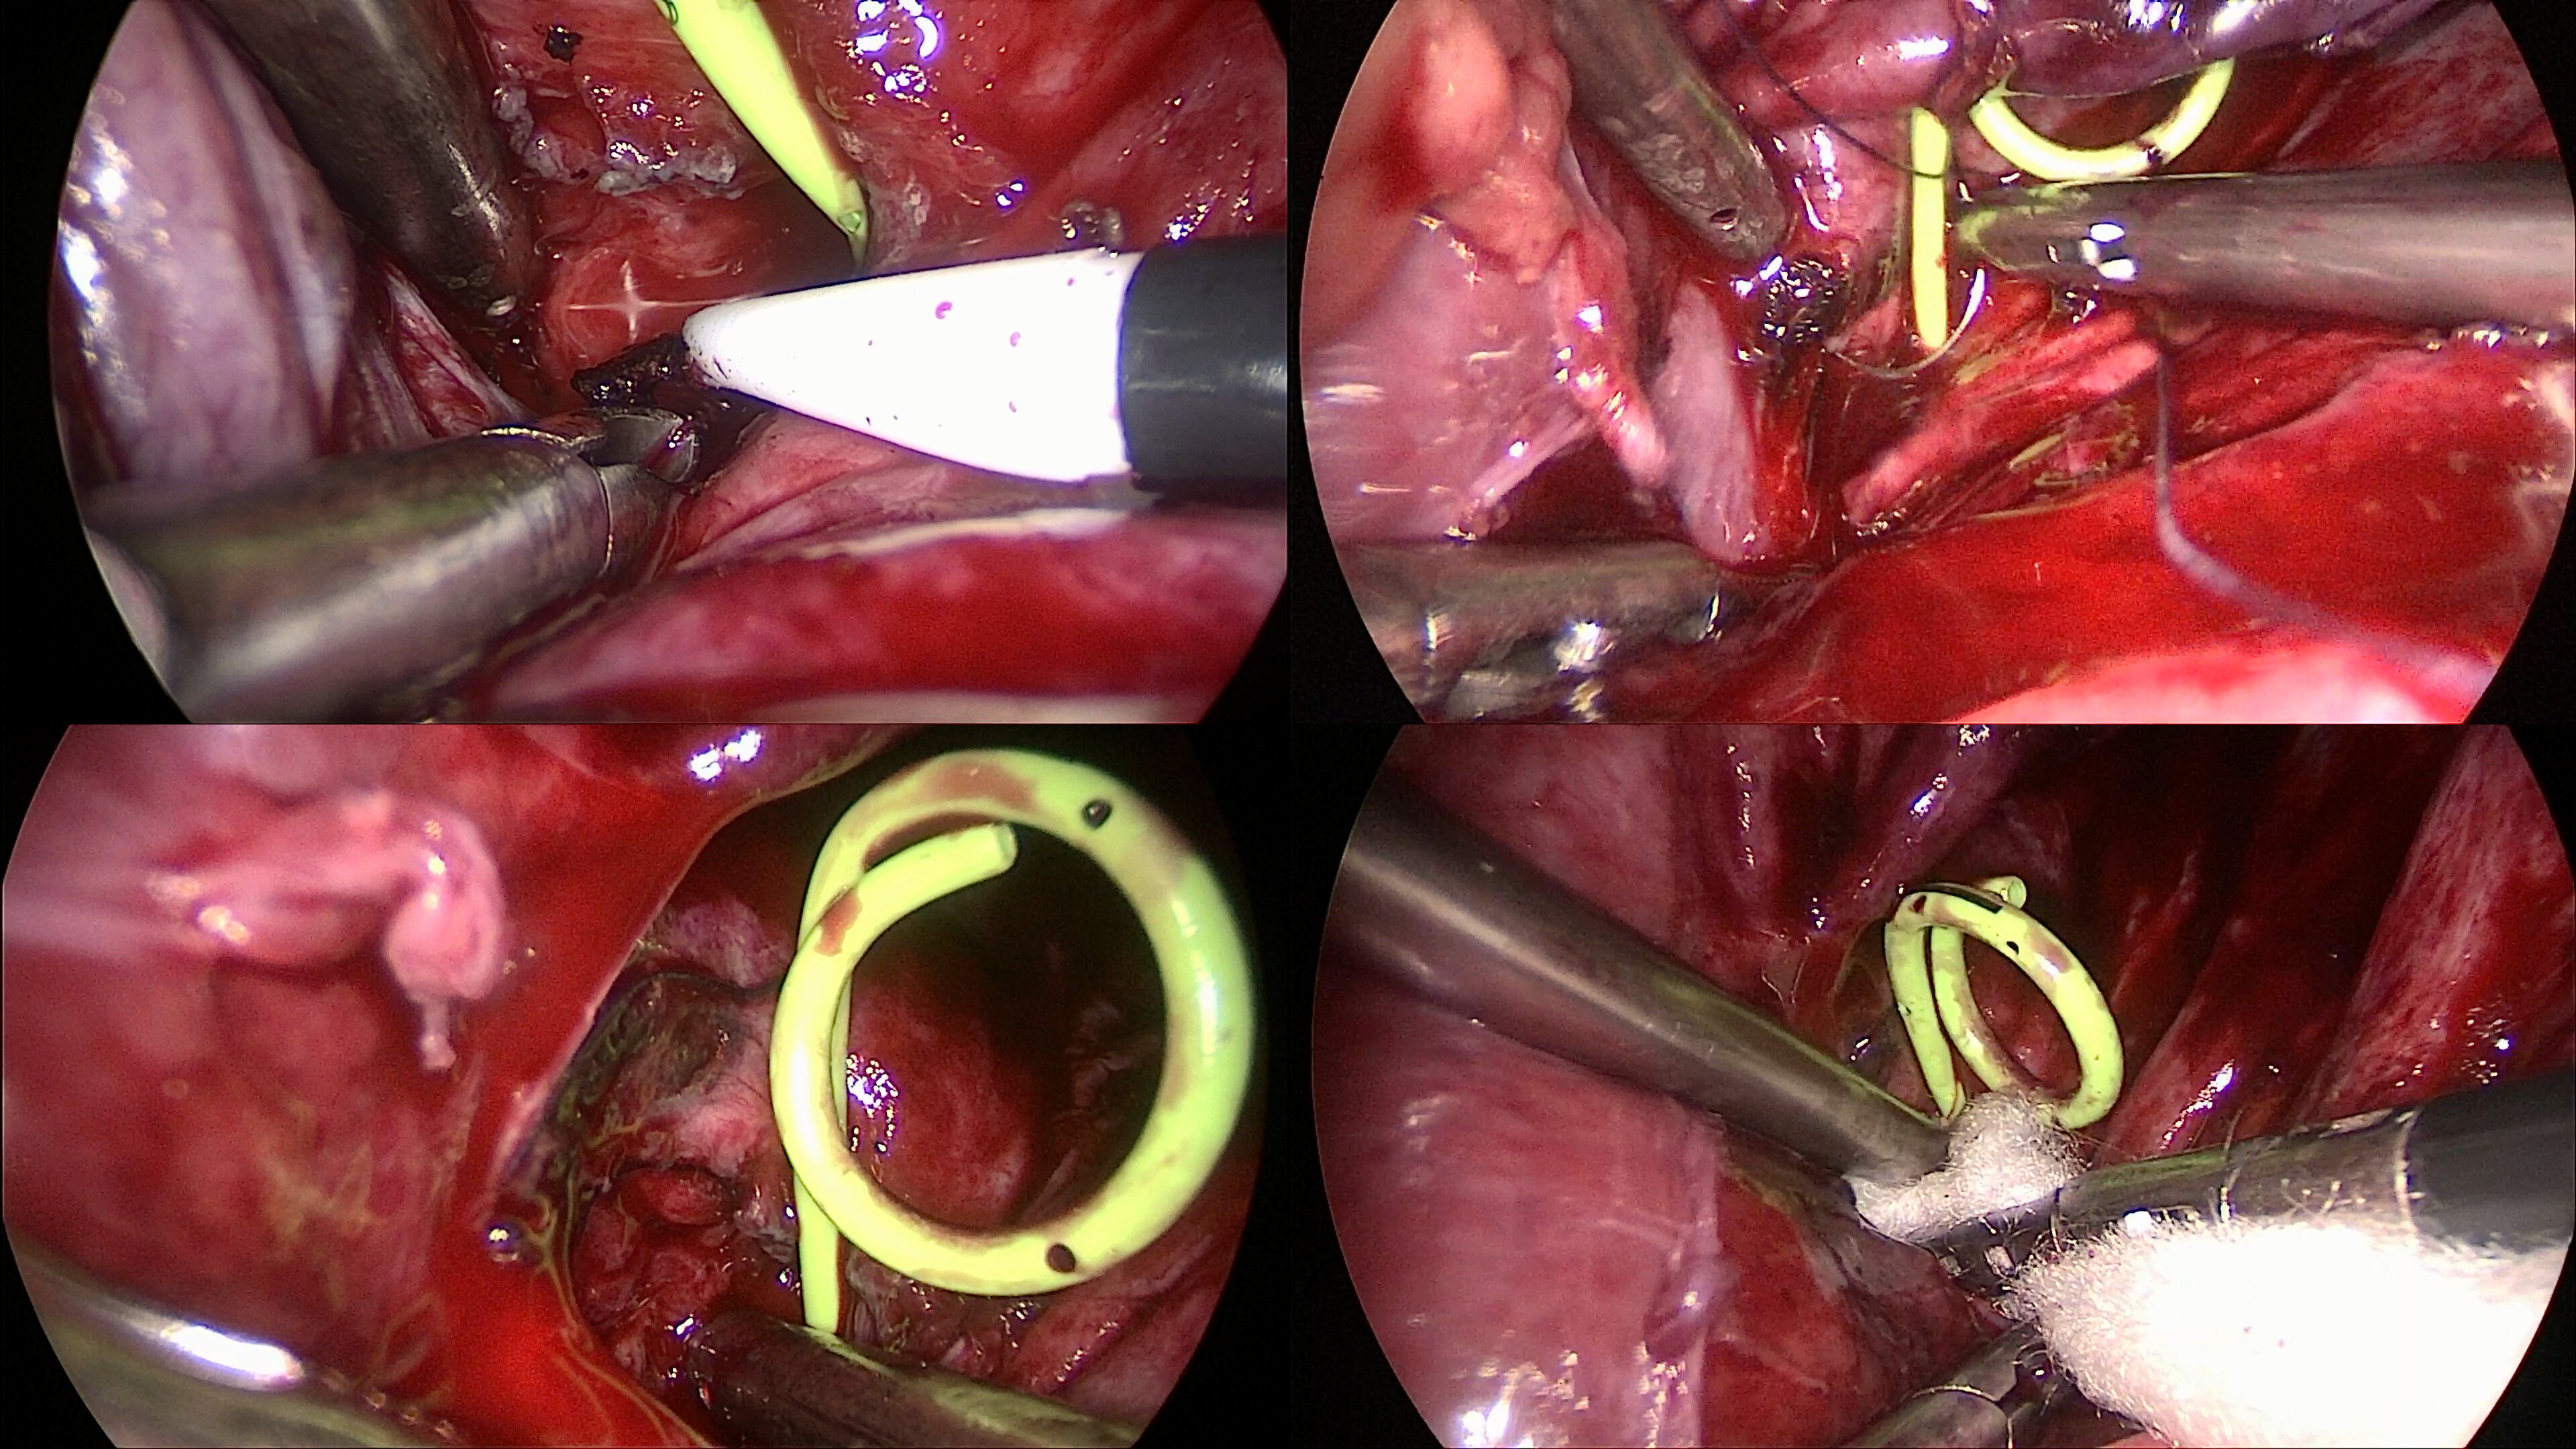

20号作品:经输尿管鞘输尿管硬镜取石治疗复杂输尿管结石

103号作品:经皮肾镜联合输尿管软镜治疗肾结石_手术

双镜联合顺行经皮肾镜联合逆行输尿管软镜治疗复杂肾结石典型病例分析